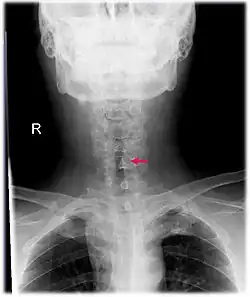

Neck AP x-ray of patient with post-intubation subglottic stenosis, as shown by the narrowing in the tracheal lumen marked by the arrow.

CT scans and MRI (magnetic resonance imaging) can help in diagnosis. X-rays can determine the location and size of the narrowed airway portion. Optical coherence tomography (OCT) can help observe the progression of the injury. Esophageal pH monitoring can help detect any acid reflux, which can worsen the condition. A laryngoscopy or an endoscope can be inserted and used to see the vocal cords, airway, and esophagus/trachea. Spirometry is a useful way to measure respiratory function. People affected by subglottic stenosis have a FEV1 of over 10.[2]